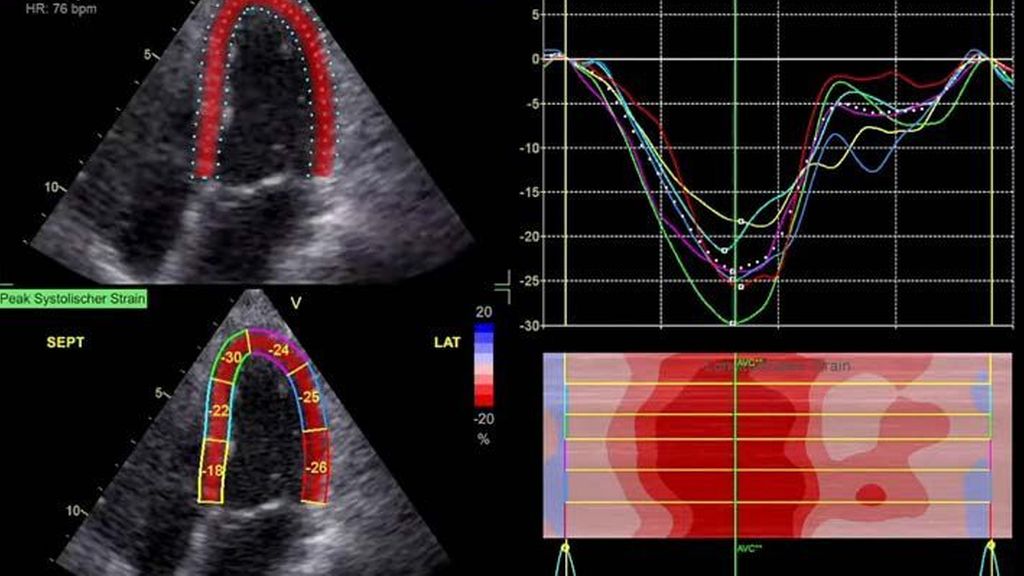

Im Echolabor des Pyhrn-Eisenwurzen Klinikums Steyr wird jede Form der Myokardwandverdickung mittels einer vollständigen Standardechokardiografie untersucht.2 Dabei wird auch ein Fokus auf die kontrastmittelunterstützte Sonografie gelegt, um die tatsächliche Dicke des Myokards zu vermessen.3 Die Verdickung sollte optimalerweise mittels 3D-LV-Massenmessung erfolgen. Die Messung im 2D-Bild ist dahingehend unterlegen. Ebenso wird jede Myokardwandverdickung mittels 2D-„strain imaging“ in der transthorakalen Echokardiografie (TTE) untersucht.4–6 Der „strain“ ist eine Messung der longitudinalen Funktion des Herzens (Video 1).

Der erste Fall beschäftigt sich mit einem Patienten mit einer hypertrophen Kardiomyopathie (HCMP). Er gibt eine deutliche Belastungsdyspnoe sowie einen ausgeprägten Leistungsknick an. Es wurde infolgedessen eine Untersuchung mittels standardisierter Echokardiografie inklusive „strain imaging“ durchgeführt. Der globale longitudinale „strain“ (GLS) mit –16% in Ruhe war gering reduziert. Es konnte kein relevanter LVOT-Gradient in Ruhe nachgewiesen werden. In der Belastungssituation (Handgrip, Valsalva, Kniebeugen und als Vorbereitung zur Untersuchung ein ausgiebiges Frühstück und Kaffee sowie ein am Vorabend konsumiertes Bier) konnte bei Kniebeugen mit einer Herzfrequenz von 126/min ein Spitzengradient bis 52mmHg dargestellt werden. Somit ergibt sich die Diagnose einer HOCMP mit einem belastungsinduzierten Gradienten. Bei bereits bestehender und ausgereizter Therapie unter Betablocker besteht die Indikation zur Therapie mittels des kardialen Myosininhibitors Mavacamten (Klasse-IIa-Empfehlung laut ESC).1 Darunter verbesserte sich die klinische Situation des Patienten deutlich, der Patient konnte uneingeschränkt Sport ausüben. Über die Zeit kam es zu einer geringen Reduktion der LV-Masse und einer geringen Zunahme des LV-„strain“. Die Belastungssituation zeigte durchwegs normale „strain“-Werte mit –20% (mit regionaler Reduktion bei Myokardwandverdickung im Sinne einer Hypertrophie). Die myokardiale Arbeit beim konkreten Patientenfall ist ebenso in Ruhe im grenzwertigen und unter Belastung im guten Normalbereich.6,8,9 Der Patient ist derzeit unter 5mg Mavacamten einmal täglich optimal eingestellt. Die EF in Ruhe ist konstant bei 50–55%. In Video 2 werden unterschiedliche Gradienten dargestellt, um eine HOCMP mit LVOTO von z.B. einer Mitralklappeninsuffizienz zu unterscheiden.Die Verdachtsdiagnose wurde mithilfe der Echokardiografie gestellt und durch das septal betonte „patchy“ LGE im MRT bestätigt.1,5

Andere Formen der Myokardwandverdickung, die mit „strain“ und MRT gut dargestellt werden können, sind einerseits die Differenzierung der Auswirkung der arteriellen Hypertonie (weiblich, 72a) bei Vorliegen einer Herzinsuffizienz mit normaler EF, einem GLS von –15,4%, einem LA-„strain“, in Reservoirphase 25% bei gering verlängerten T1-Zeiten im MRT. Andererseits kann Steroidabusus (männlich, 44a) zu einem reduzierten „strain“ mit gering verlängerten T1-Zeiten und einer Normalisierung der bildgebenden Befunde nach 2 Jahren nach Absetzen führen bzw. eine Mitochondriopathie (männlich, 32a) zu einer unklaren Myokardverdickung mit diffus reduziertem „strain“ und reduzierter LV-Funktion.4,11,12